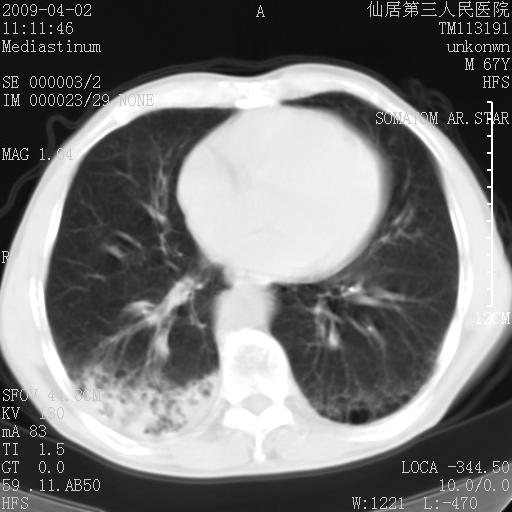

患者老年男性,乏力畏寒来诊,摄胸片示右下肺感染性病变,抗炎两周后复查胸片,无好转有进展。

后做ct平扫表现如下:

考虑右肺炎症可能性大,不除外细支气管肺泡癌

是否还要考虑肺间质纤维化,建议hrct扫描。

病灶呈蜂窝征,纵隔多个淋巴结肿大;肺泡癌需考虑

我认为普通的感染应该可以除外,间质性肺炎可能性较大,但如何解释纵膈的淋巴结肿大呢

考虑双肺间质性改变(间质纤维化?)伴右肺下叶感染。